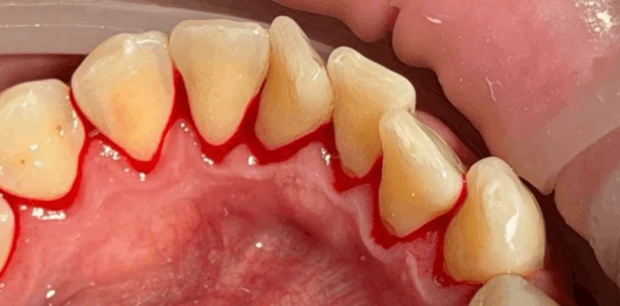

Профгигиена

Профессиональная гигиена зубов

Пациент Ф., 27 лет обратился с жалобами на периодическую кровоточивость десен при чистке зубов и на скученность зубов. Проведена профессиональная гигиена полости рта, пациент направлен на ортодонтическое лечение.